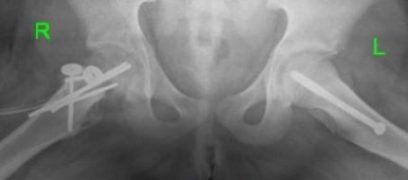

Ребенку 7 лет с болезнью Легга – Кальве – Пертеса в стадии разгара фрагментации справа с тотальным поражением эпифиза и подвывихом бедра произведено хирургическое вмешательство на правом тазобедренном суставе:

Остеотомия таза по Salter в сочетании с корригирующей (варизирующей) укорачивающей остеотомией бедра.

Рентгенограммы тазобедренных суставов

Ребенку 12 лет с юношеским эпифизеолизом головки бедренной кости (тяжелая форма справа и легкая форма слева) произведены хирургические вмешательства на обоих тазобедренных суставах:

Модифицированная операция Dunn справа.

Фиксация эпифиза головки бедра винтом слева.

Рентгенограммы тазобедренных суставов